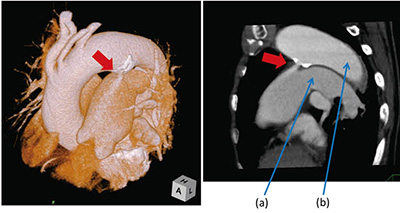

[動脈管開存症(PDA)]

胎児の時に存在している動脈管は、通常では出生後は不要となり、生後2〜3日で閉じるが、動脈管が閉じずに残存してしまう場合がある。動脈管開存症(PDA)は、動脈血の一部が肺動脈に流れ込む病気である。図6の症例は、PDA精査目的での検査であり、撮影範囲が限られていたためVolume Scanを用いて検査を行った。血管病変には、Slab-MIPを用いて画像の提供を行っている。PDAは、年齢とともに石灰化を来すため、MIPを用いることで石灰化の情報もわかりやすく画像提供できる。このように、さまざまな画像再構築を行う場合にも、それぞれの用途に分かれたソフトがあり、最適な画像再構築によって画像提供を行うことができている。

図6 動脈管開存症(PDA)の症例

a:肺動脈 b:大動脈

大動脈から肺動脈に流入する動脈管を矢印(↓)で示す。

PDAの大動脈起始部に石灰化を認める。